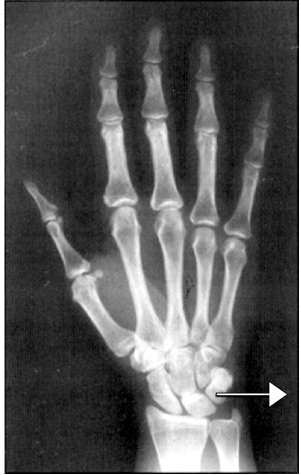

Ao se realizar um raio X da mão em Postero Anterior, marque a alternativa em que a estrutura está em destaque:.